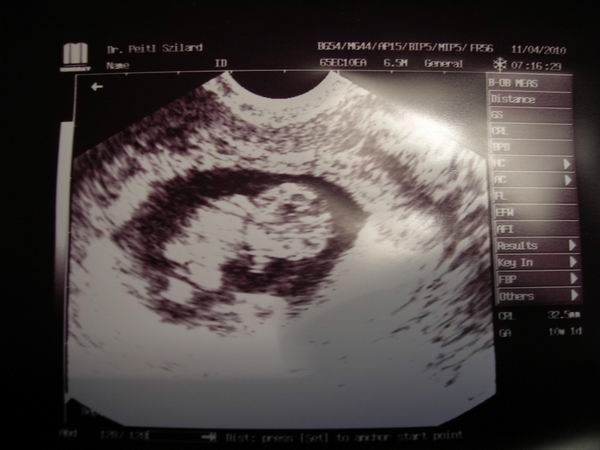

Én mindig csak az u.h-kat várom, de izgulok is miattuk nagyon.Én már olyan rég láttam a babánkat, több, mint 3 hete

Ági, gyönyörűséges a babád